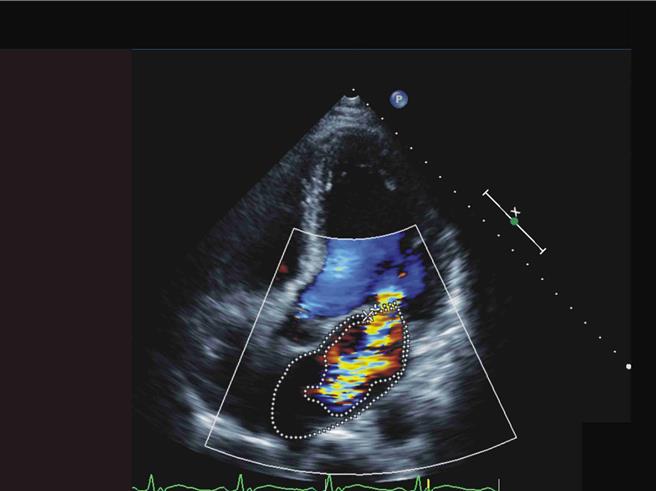

陳姓果農隨即被宣告病危,送入加護病房。在馬拉松式的照護下,緊急心臟超音波檢查揭示二尖瓣的嚴重閉鎖不全,血液培養不到8小時就長出金黃色葡萄球菌,顯示心臟深受感染,讓醫療團隊震驚不已。彰基心臟外科主任醫師陳映澄緊急會診後,決定進行微創二尖瓣人工瓣膜置換術。

陳映澄表示,手術過程中,在患者心臟瓣膜的深處發現化膿和細菌贅生物,幸好手術成功,患者不僅在1天後順利拔管,更在短短一周內轉入普通病房,經過完整的抗生素治療後,1個月後出院回歸正常生活。